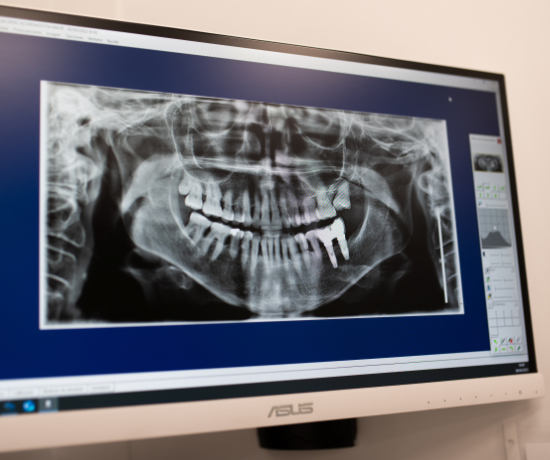

La periodoncia es el campo de la odontología que se encarga de la prevención, el diagnóstico y el tratamiento de las enfermedades periodontales, que son aquellas que afectan a los tejidos blandos y duros que rodean y sostienen los dientes (encía, hueso alveolar, cemento radicular y ligamento periodontal).

- Periodontitis: es una forma más avanzada de enfermedad periodontal. En este caso, la infección se extiende hacia el hueso y el tejido de soporte del diente, lo que puede derivar en movilidad dental e incluso pérdida de piezas dentales. Esto se debe a que, si no se trata adecuadamente, puede causar un daño permanente en dichos tejidos.

- Instrumentación subgingival (raspado y alisado radicular): es un tratamiento más avanzado, por lo que se pauta en casos de periodontitis. También sirve para retirar la placa bacteriana y el sarro acumulados pero permite incidir debajo de la línea de la encía para limpiar las bolsas periodontales (pequeños depósitos que se forman en el interior de la encía, a la altura de las raíces de los dientes, y que contienen bacterias).

- Regeneración periodontal ósea: restaura la inserción perdida, lo que es imprescindible para aportar sujeción al diente y evitar que se mueva o se pierda.